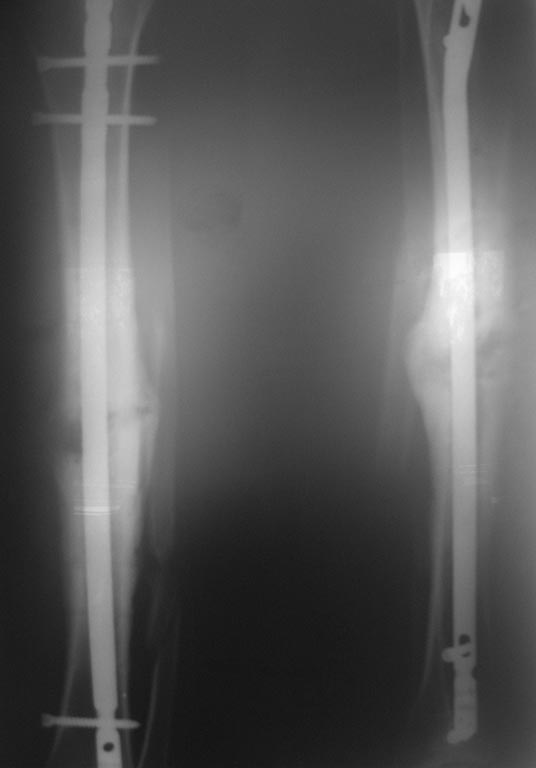

Пациент 26 лет. Травма в сентябре 2013 года в результате ДТП (сбит машиной)- закрытый перелом обеих костей правой голени. Операция в соседней ЦРБ- открытая репозиция, остеосинтез блокируемой пластиной (первичные и послеоперационные снимки утрачены). Предписанный режим не соблюдал. Обратился к нам в октябре по поводу поломки фиксатора (снимок 1). Выполнено 31.10.13: удаление металлоконструкций, БИОС неканюлированным штифтом DC с рассверливанием. П/операционный период гладкий. В январе обратился по поводу возникновения болей в месте перелома, отека, появления свища на внутренней поверхности голени. 23.01.14- ревизия свища, секвестрэктомия (множество мелких секвестров в мягких тканях вокруг мозоли). В дальнейшем рана велась при помощи VAC, зажила без осложнений. Около месяца назад вновь появились боли в области формирующейся мозоли, во втянутом рубце сформировался свищ, через который эвакуировалось несколько мелких секвестров. В настоящий момент свищ закрылся, боли несколько уменьшились. В анализах- СОЭ-16 мм/час, СРБ-28, лейкоциты крови- 6,4. Последние снимки и КТ представлены. Вопрос банален- что делать дальше? Большого опыта в лечении такой патологии не имеем. Спасибо всем откликнувшимся.P.S. За качество снимков прошу прощения (снимал на телефон).

На рентгенограммах с гвоздем иммется диастаз м/у отломками б/берцовой кости, сращения м/берцовой кости похоже так же нет. Поэтому в первую очередь необходимо выполнить динамизацию. В противном случае в скором времени можно ожидать обострения воспалительного процесса, более того Вы получите как минимум перелом блокирующмх винтов, а может и самого гвоздя.